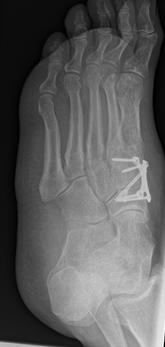

4.- 06/2017 nach Rearthrodese

Die Stabilisierung erfolgte nunmehr mittels Platte und einer externen Zugschraube. Es wurde wiederum Knochenersatzmaterial angelagert.

Bei einer Verlaufskontrolle im Juli 2017 ergab sich bei der Röntgenuntersuchung eine Fehllage einer Plattenschraube, die damit das TMT 2 überbrückte.

5.- 07/2017 Schraubenfehllage : Schraube erreicht Basis MT2 und überbrückt TMT 2